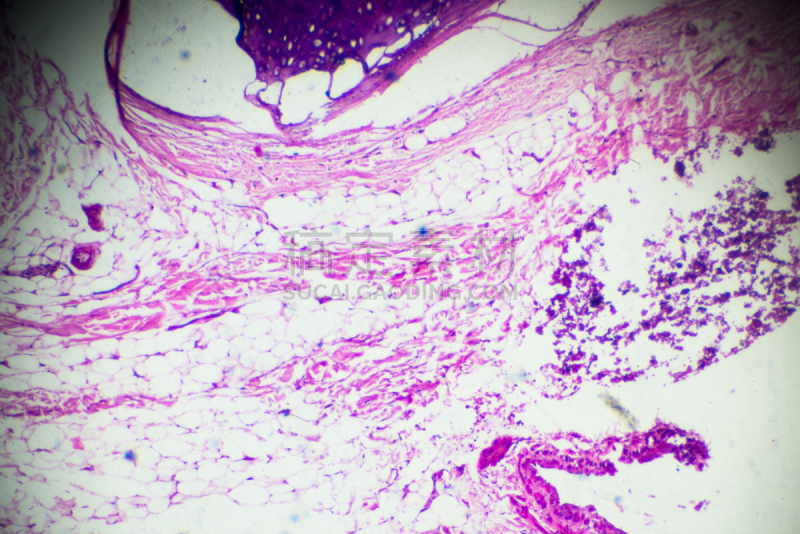

蓝色鳞状细胞详情